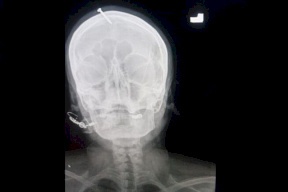

تفاصيل وفاة طبيبة مصرية بخطأ طبي.. "دخلت على رجلها خرجت ميتة"

صدى نيوز - روت أم مصرية مكلومة تفاصيل وفاة ابنتها الطبيبة مروة صلاح، البالغة من العمر 40 عامًا، نتيجة إهمال طبي جسيم تعرضت له خلال إجراء عملية منظار في المرارة، لتخرج منها إلى مثواها الأخير، تاركة طفلين في عمر الزهور.

وقالت الحاجة فاتن "بنتي دخلت على رجلها، خرجت ميتة"، وأضافت لموقع &quo...